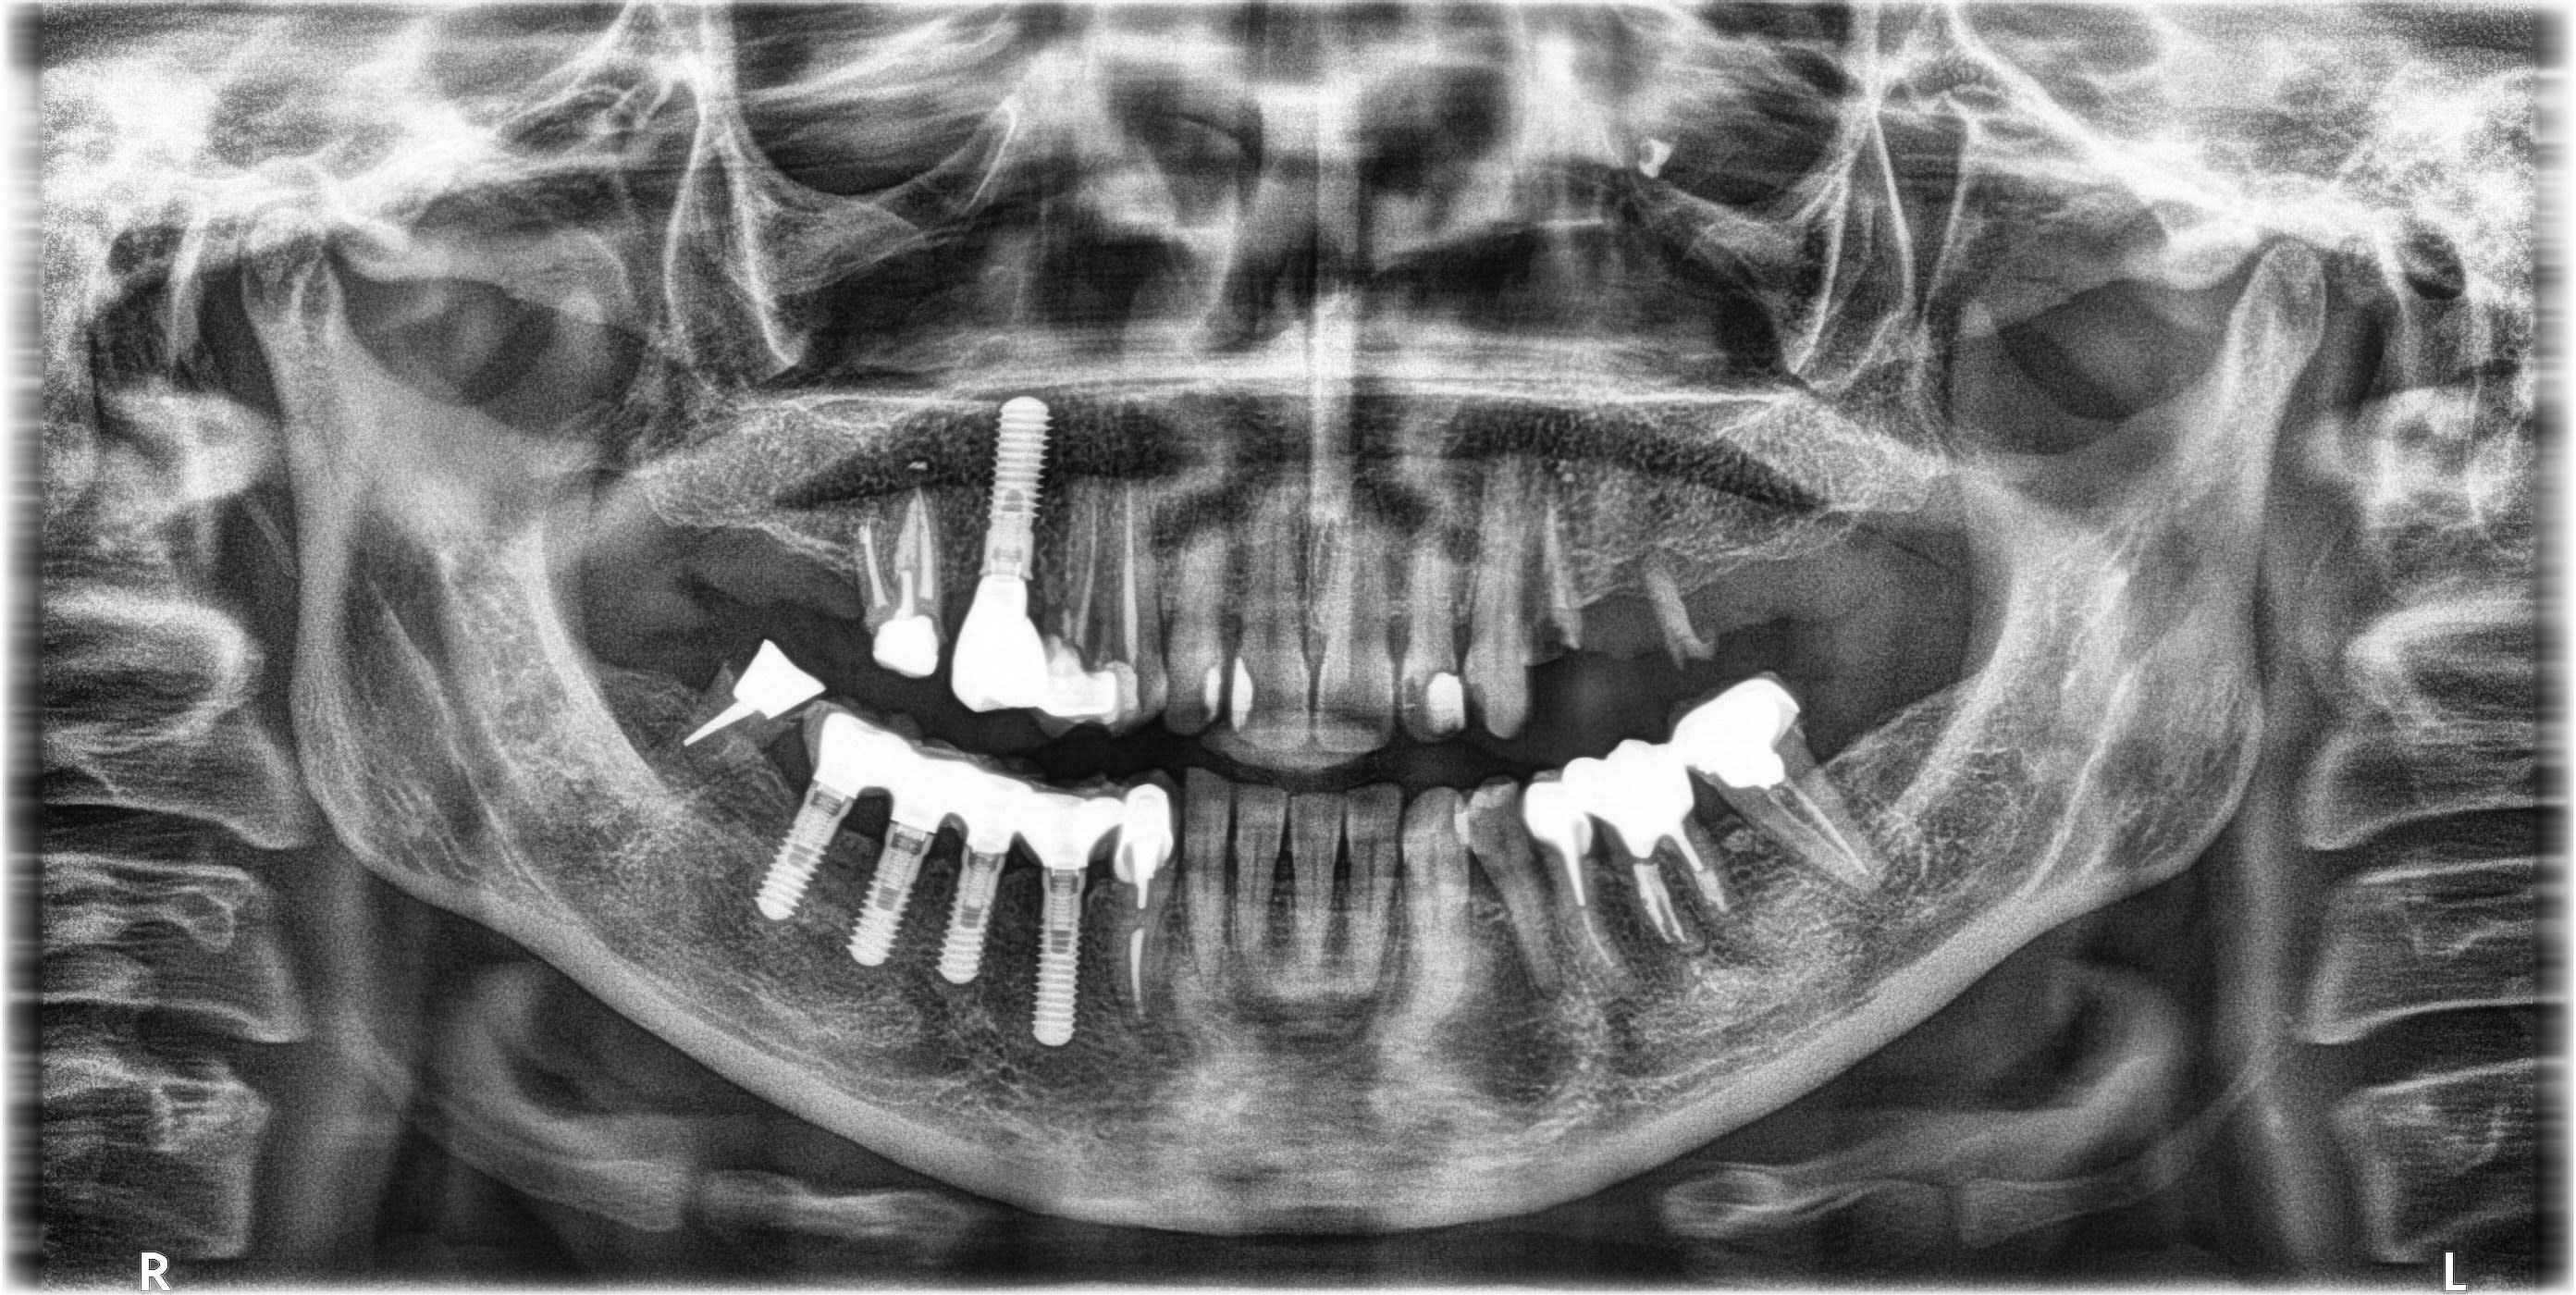

Bonjour, la couronne sur l'implant en 15 est dévissée, je n'ai pas retrouvé cet implant sur whatimplantisthat, j'ai donc besoin de vos lumières (enfin surtout celle de pluton!!!)

c'est des IDI

http://osseosource.com/dental-implants/product_info.php?manufacturers_id=118&products_id=850